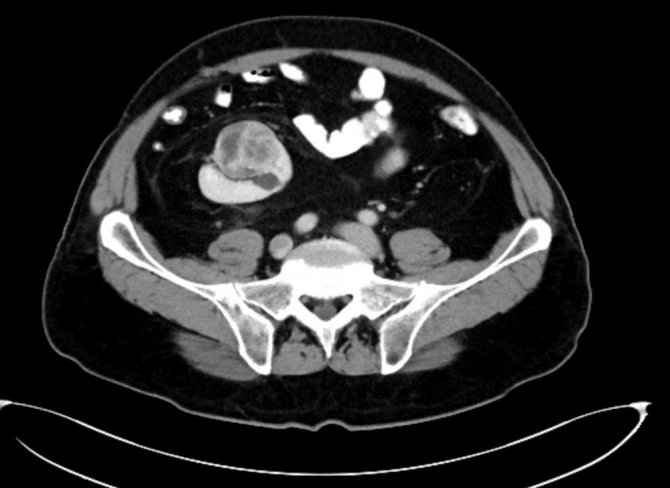

Karın ağrısı ve idrarda kan görülmesi şikâyetiyle, Trakya Üniversitesi Hastanesi Üroloji Polikliniğine başvuran ve yapılan kontroller sonrası sağ böbreğinin çok nadir görülen şekilde karnın alt kısmında, bağırsaklarının arkasında olduğu ve üzerinde bir tümör de olduğu tespit edilen 70 yaşındaki S.K adlı hasta, Trakya Üniversitesi Hastanesi'ne başvurana kadar doğuştan tek böbreği olduğunu bildiğini ve iki böbreği olduğunu öğrendiğinde şaşkınlığını gizleyemediğini belirterek, kendisini tedavi ederek hayata döndüren doktorlara teşekkür etti.

Başarıyla sonuçlanan operasyon, dünyada bir ilk olma özelliği taşıyor. Literatürde, benzer bir vak'a ile 2018 yılında Japonya'da karşılaşıldığı ve oradaki ameliyatın açık tekniklerle yapıldığı bilgisini aktaran Doç. Dr. Hakan Akdere, dünyada ikinci Türkiye'de ise ilk kez böyle bir vak'a ile karşılaşıldığını belirtti. Hastanın sağ böbreğinin, dünyada örneği çok nadir görülen bir yerde olduğunu ve bunun operasyonun önemini artırdığını hatırlatan Doç. Dr. Hakan Akdere, "Lumbal böbrekte tümörü olan bir hastayı, kapalı yöntem ile (laparoskopik) böbreği koruyarak, böbrek damarlarını geçici olarak kapatmadan ve sadece tümoral kitleyi çıkararak başarılı bir operasyonla sağlığına kavuşturup 3. gün hastayı taburcu ettik" dedi. Literatürde, 2018 yılında Japonya'da, lumbal böbrekte kitlesi olan bir hastanın açık teknik ile ameliyat edildiği ve böbreğinin tamamen alındığı bilgisi var. Dünyada daha önce laparoskopik cerrahiyle ilgili yaklaşımların mevcut olduğunu ancak böyle bir vak'ada, bu yöntemle yapılan ameliyatın ilk kez Türkiye'de, Trakya Üniversitesi'nde gerçekleştiğine ve tıp literatürüne geçecek bir yöntemle hastanın sağlığına kavuştuğuna dikkat çeken Doç. Dr. Hakan Akdere, "Böbrek tümörü tedavisinde, kanserli dokunun yayılımına göre böbreğin tamamının veya böbreği koruyarak sadece kitlenin alınması gerektiğini" vurguladı. Bu tür ameliyatları açık, Robotik Cerrahi ya da Laparoskopik cerrahi ile gerçekleştirmek mümkündür. Trakya Üniversitesi Tıp Fakültesi Üroloji A.B.D. olarak, lumbal böbrekte kitlesi olan bir hastayı, dünyada ilk kez "laparoskopik" cerrahi ile sağlığına kavuşturduk. Bu yöntem, bu tür bir vakada ilk kez uygulanan, henüz literatürde yeri olmayan bir başarıdır" ifadelerini kullandı.